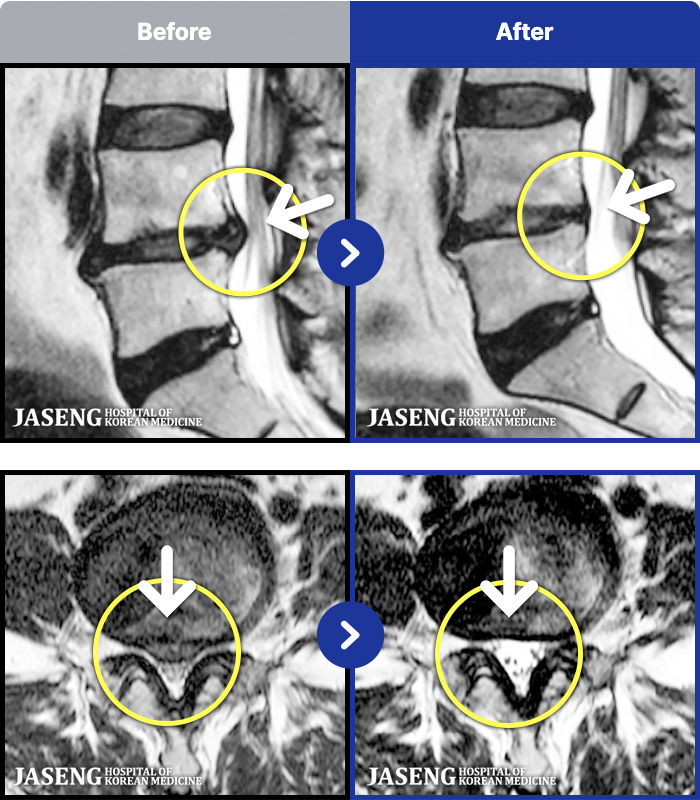

- MRI ġ

MRI ġ

1,237 MRI ũ ʸ Ȯϼ.